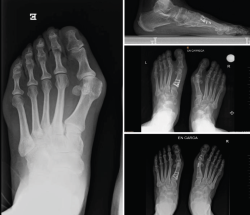

Figura 2. Detalles quirúrgicos de la osteotomía de apertura medial.

No se objetivó ningún caso de metatarsalgia de transferencia ni de pseudoartrosis. En las Figuras 2 y 3 se pueden ver detalles quirúrgicos de las osteotomías de apertura y cierre.

Figura 3. Detalles quirúrgicos de la osteotomía de cierre lateral.